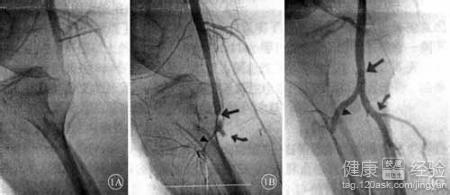

動脈栓塞是指血塊或進入血管內的異物成為栓子,導致動脈血不能流通,導致相應肢體或器官缺血以至壞死的一種病理過程。患者一開始往往表現為麻木,疼痛,肢體運動障礙等。這種病往往發生的很突然,如果發病一小時以內治愈可能性比較大。如果治療遲了,只能緩解一下病情,至少不讓眼睛失明。患者平時也要特別注意眼睛的保護。所以及早診斷和治療相當重要。

2這種病往往發生的很突然,所以及早診斷和治療相當重要。患者一開始往往表現為麻木,疼痛,肢體運動障礙等。眼底中央動脈栓塞左眼失明想治愈可能比較困難,如果發病一小時以內治愈可能性比較大。

3所以,我們講,患者有動脈栓塞的情況發生時,應該立即就醫,及早治療,這對治愈的幫助很大。如果治療遲了,只能緩解一下病情,至少不讓眼睛失明。患者平時也要特別注意眼睛的保護。